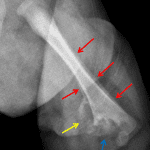

- Extensive bone destruction involving the medial two-thirds of the distal femoral metaphysis with possible additional involvement of the medial aspect of the epiphysis

- Soft tissue extension adjacent to the osseous destructive changes with developing heterotopic ossification

- Periosteal reaction along the femoral shaft with faint periosteal reaction along the proximal tibia

- Osteomyelitis

Extensive bone destruction involving the medial two-thirds of the distal femoral metaphysis with possible additional involvement of the medial aspect of the epiphysis and periosteal reaction along the femoral shaft. Findings are most concerning for osteomyelitis, particularly given the clinical history. Associated septic arthritis of the knee cannot be excluded on this study. Consider MRI for further evaluation.

Soft tissue extension adjacent to the osseous destructive changes with developing heterotopic ossification. MRI could also evaluate for associated soft tissue abscess.

Faint periosteal reaction along the proximal tibia may be reactive; however, infectious involvement of the tibia is not excluded.